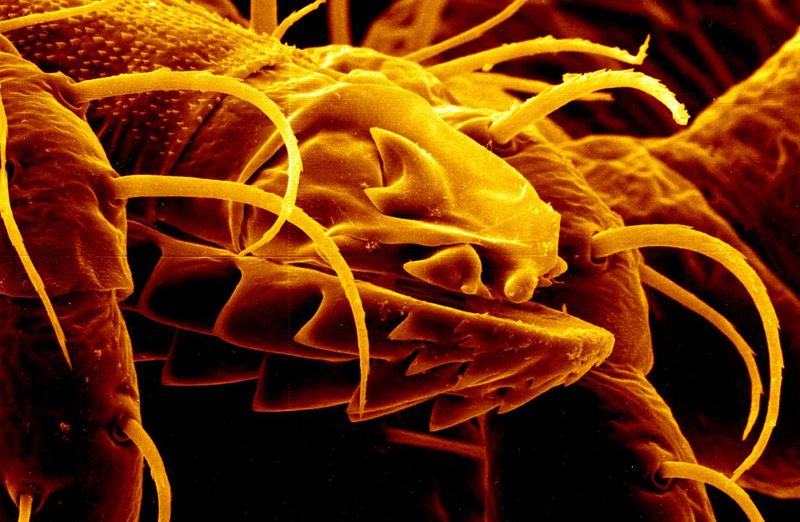

The team, based at Osaka Metropolitan University in Japan, developed a method of screening over 1,800 different chemicals to find those that could act directly on HSCs. One stood out: Lawsone, a component of the henna tree.

The study team discovered that the lawsone extract had the potential to inhibit the activity of HSCs, and in vitro experiments suggested it could have a favorable safety profile with low toxicity. They therefore decided to take it forward to experiments in a mouse model. Mice treated with lawsone exhibited decreased levels of various markers of liver fibrosis, and an increase in a marker of HSC antioxidant function.